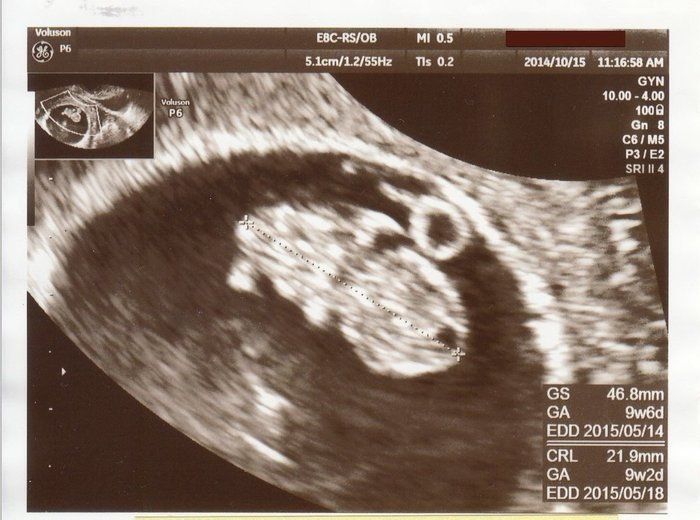

セイコさんの妊娠9週目のエコー写真 赤ちゃんぽくなって来ました

頭やおなか、短い手足も見えて来て、生き物っぽくなってきました。元気な姿を確認できるとほっとします。結果、問題はなかったのですが、私の体質的に子宮が大きくなる際に少し出血するようで、この頃はおりものに色がついているのが心配な日々でした。